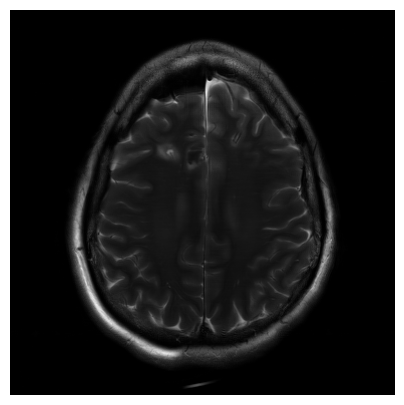

Qualitative.

The visual inspection of the images reconstructed (available in Fig. 2) at acceleration factor 4 shows little to no visible difference with the ground truth original image. However, when increasing the acceleration factor to 8, we can see that smoothing starts to appear which leads to a loss of structure as can be seen in Fig. 3.

| T1 PSNR: 41.56 SSIM: 0.9506 | T2 PSNR: 40.68 SSIM: 0.9554 | FLAIR PSNR: 39.60 SSIM: 0.9321 | T1POST PSNR: 42.53 SSIM: 0.9683 |